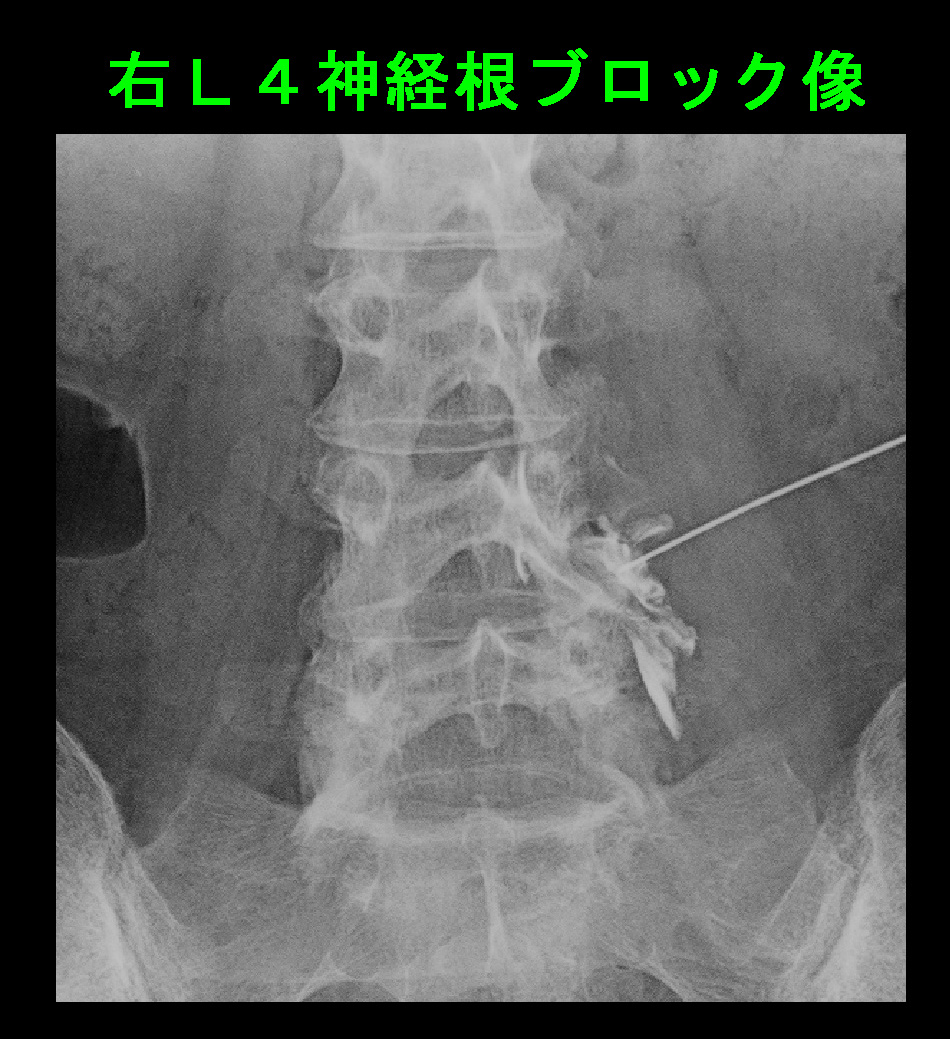

以後、受診がなかったため、5月18日(初診から24日後)に電話で様子を尋ねると、症状は軽減していないが、注射は怖いと言っていました。私は再度最も効果が期待できる治療はブロックであることを伝えています。患者さんは6月15日(初診から7週後)に再診され、良くならないからブロックを受けてみるということでした。この時点で右股関節痛は軽減しており、右臀部から大腿部背側痛となっていました。右L4神経根ブロックを施行しています。

60才女 RB.jpg

6月23日(ブロック後1週)で受診され、VAS6の症状は0となり、何も困っていないということでした。患者さんは注射の痛みはさほどでなく、医師の勧めを無視して我慢していたのはバカみたいだったと述べていました。